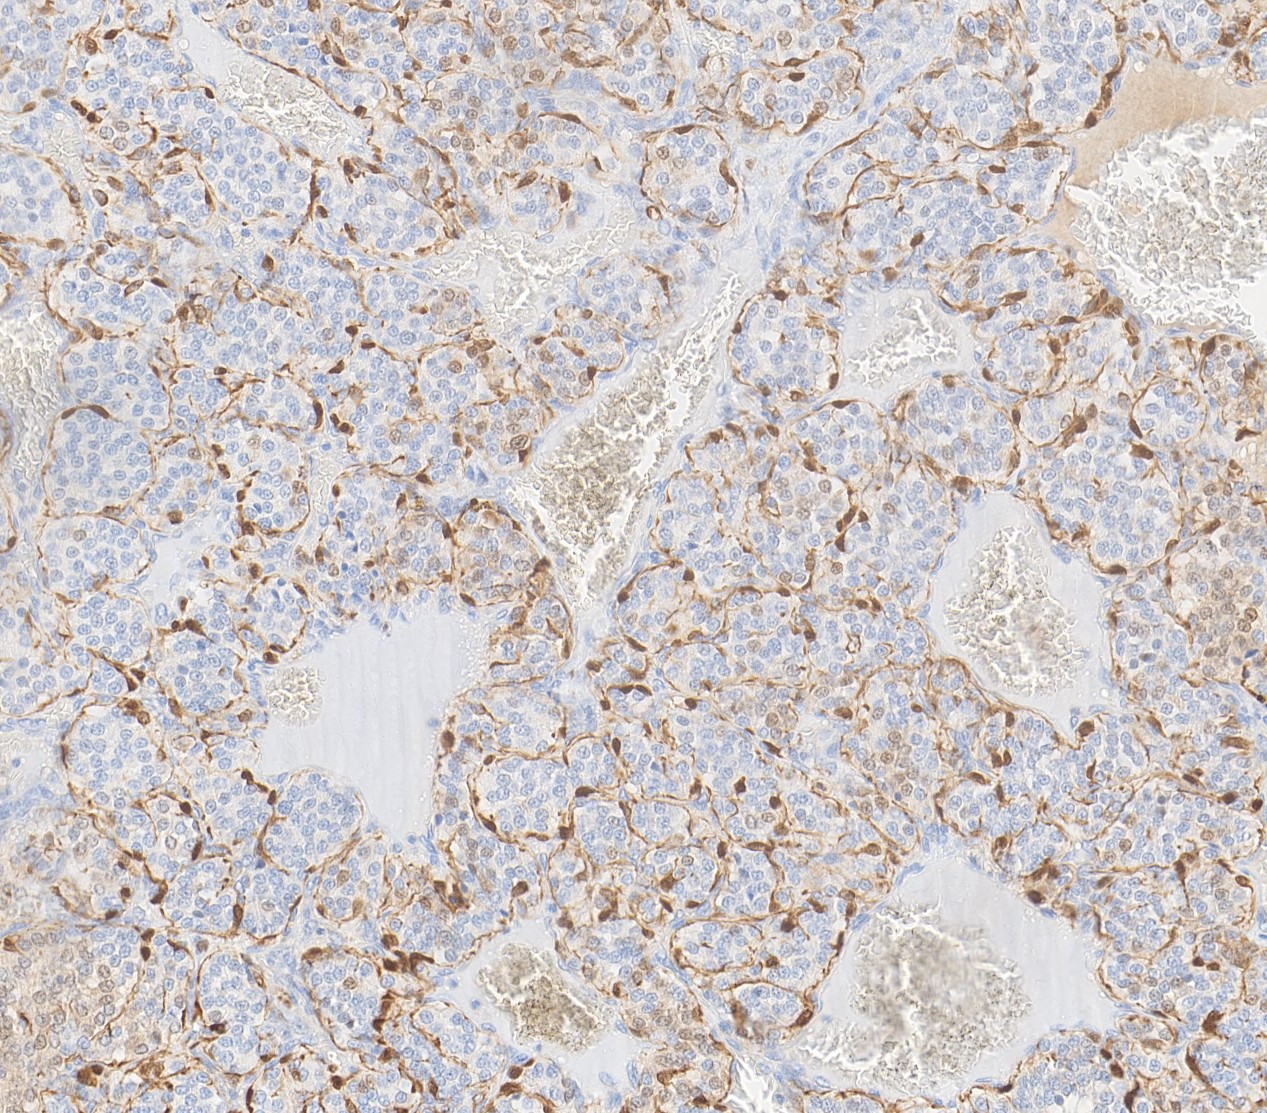

Special stains:

Carotid body paragangliomas are slow growing, well circumscribed tumors with a reddish-brown, firm cut surface. Hemorrhage and cystic degeneration may be seen. On microscopy, nests of oncocytic cells ("zellballen"), often with prominent intranuclear cytoplasmic pseudoinclusions, are surrounded by a fibrovascular network including small spindled sustentacular cells. As demonstrated by this case, an organoid growth pattern is most common in head and neck paragangliomas, but trabecular and solid growth, spindled areas, pigmentation, stromal sclerosis and even amyloid deposition have been described (Head Neck Pathol 2015;9:300). The sustentacular cells stain with S100 and the tumor cells with neuroendocrine markers (synaptophysin, chromogranin, CD56). A reticulin stain will highlight the fibrovascular network. Management is surgical resection (Arch Pathol Lab Med 2014;138:182).

Special stains:

Carotid body paragangliomas are slow growing, well circumscribed tumors with a reddish-brown, firm cut surface. Hemorrhage and cystic degeneration may be seen. On microscopy, nests of oncocytic cells ("zellballen"), often with prominent intranuclear cytoplasmic pseudoinclusions, are surrounded by a fibrovascular network including small spindled sustentacular cells. As demonstrated by this case, an organoid growth pattern is most common in head and neck paragangliomas, but trabecular and solid growth, spindled areas, pigmentation, stromal sclerosis and even amyloid deposition have been described (Head Neck Pathol 2015;9:300). The sustentacular cells stain with S100 and the tumor cells with neuroendocrine markers (synaptophysin, chromogranin, CD56). A reticulin stain will highlight the fibrovascular network. Management is surgical resection (Arch Pathol Lab Med 2014;138:182).